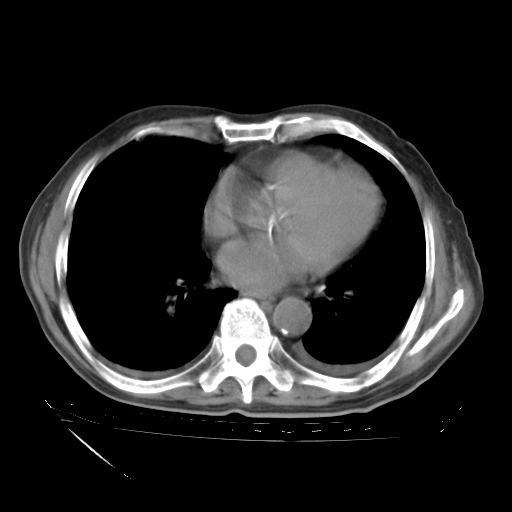

经过24天治疗,岳父的病情基本稳定。生活基本可以自理,可以下床活动。呼吸困难早已消失。体温基本正常。

只是甲强龙用80mg时血小板升到正常,改为60mg后又降到63×10*9/L。

主要治疗甲强龙80mg×14天,60mg×10天;同时抗结核(异烟肼+利福平+乙胺丁醇)。环磷酰胺0.1 tid 10天。

特别感谢胡教授、高管、桃子版主给出关键的治疗建议。桃版把所有肺部影像和全部临床资料请所在医院呼吸科、感染病科、结核科、临床免疫科专家会诊。临床免疫科专家制定了完整的治疗方案。